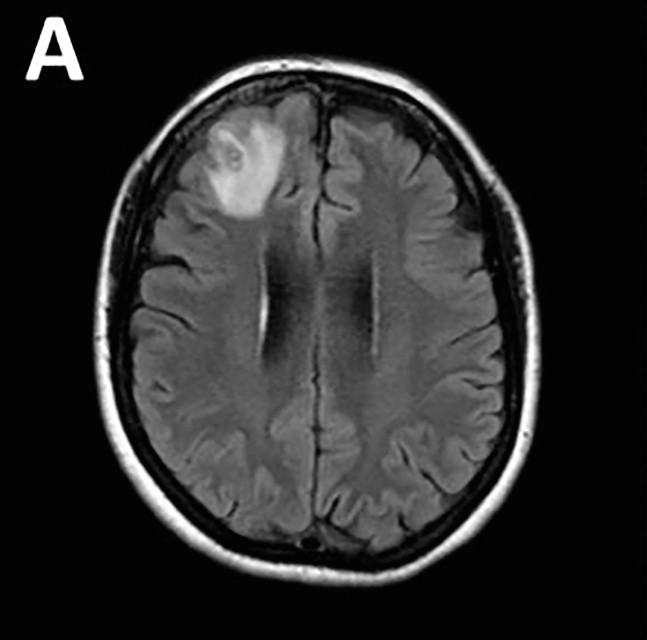

Baffled doctors performed an MRI scan on the 64-year-old Australian woman after she began suffering memory lapses, noticing an “atypical lesion” at the front of her brain.

It was an eight-centimetre (three-inch) roundworm, called Ophidascaris robertsi, which researchers said was a common parasite in kangaroos and carpet pythons — but not humans.

She was re-admitted to a hospital three weeks later when her condition did not improve, and underwent various treatments until brain scans revealed a lesion and an open biopsy was performed in June 2022.

“We noted a stringlike structure within the lesion, which we removed; it was a live and motile helminth,” the findings said.